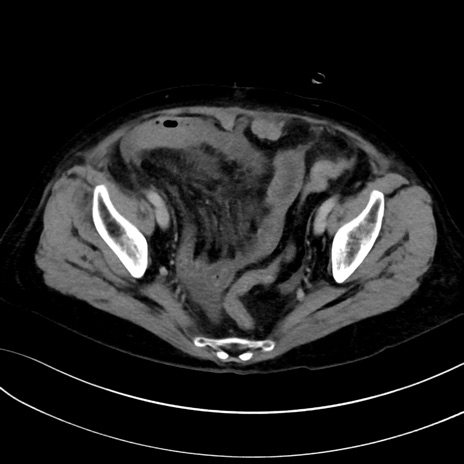

症例13 CT(横断像)1日半後